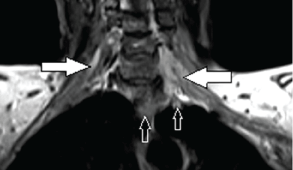

| Figure 17: A 65-year-old female with left superior sulcus metastatic breast carcinoma with diffuse BP involvement. Coronal post contrast T1-weighted MR image shows infiltrative enhancing soft tissue along the BP (solid arrows) bilaterally, left > right. On the left side, this enhancing soft tissue extending from left lung apex (open arrows) to BP. | ||